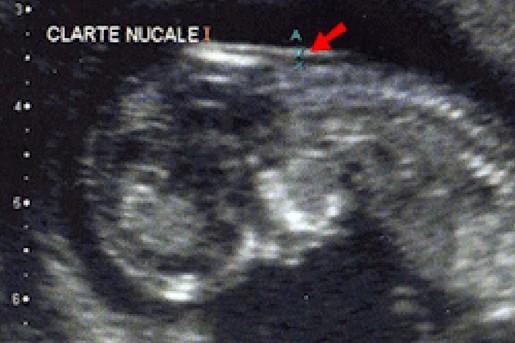

Mme Kamira Semai de l’université de Tuviret, a elle, axé son intervention sur l’importance de la prévention et la préparation psychologique de la future maman de l’enfant trisomique, mettant l’accent surtout sur l’importance du suivi obstétrique des femmes en cours de grossesse pour un dépistage de la maladie in utéro par le biais d’échographie permettant la mesure de la clarté nucale, indice déclencheur d’autres examens plus poussés si la mesure se révèle anormale pour le stade de développement du fœtus entre les 10e et 14e semaines d’aménorrhées.